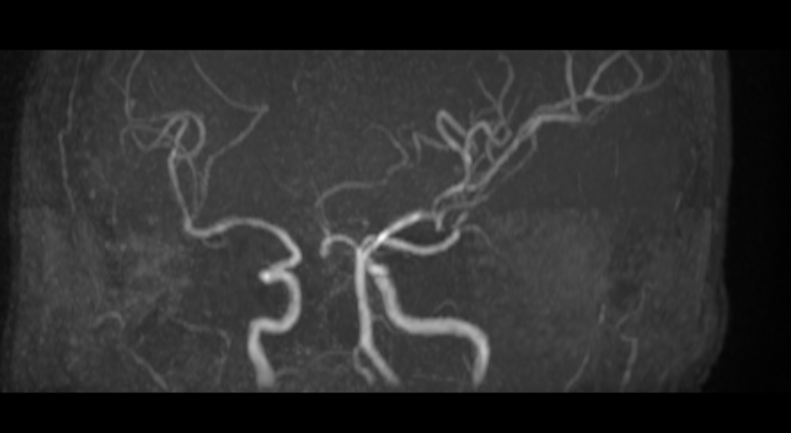

Ngay lập tức, bệnh nhân được chụp MRI sọ não, kết quả cho thấy tắc động mạch cảnh trong – não trước – não giữa bên trái, đặc biệt tắc động mạch não trước đoạn A2 phải, gây nhồi máu não ổ bán cầu trái.

Phim MRI trước can thiệp.